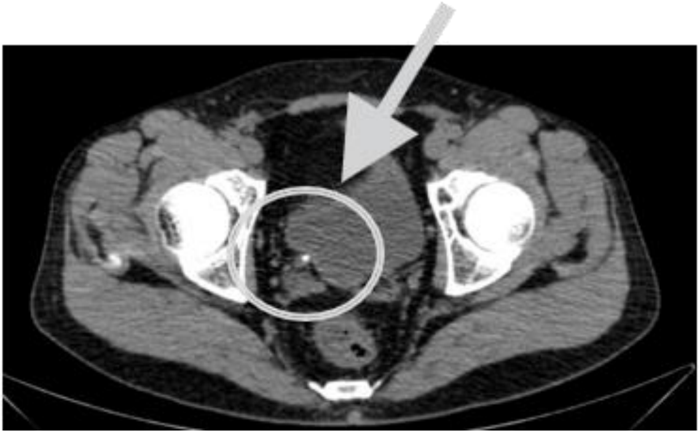

Após ver a tomografia e confirmar a hipótese diagnóstica mais provável para este caso, cite o próximo passo para o tratamento: